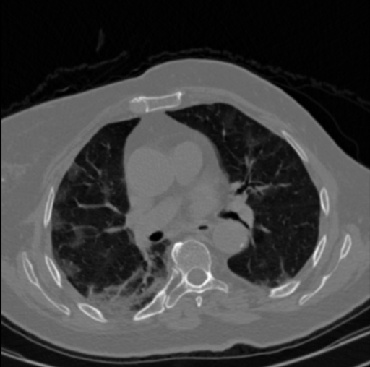

Early and reliable COVID-19 diagnosis based on chest 3-D CT scans can assist medical specialists in vital circumstances. Deep learning methodologies constitute a main approach for chest CT scan analysis and disease prediction. However, large annotated databases are necessary for developing deep learning models that are able to provide COVID-19 diagnosis across various medical environments in different countries. Due to privacy issues, publicly available COVID-19 CT datasets are highly difficult to obtain, which hinders the research and development of AI-enabled diagnosis methods of COVID-19 based on CT scans. In this paper we present the COV19-CT-DB database which is annotated for COVID-19, consisting of about 5,000 3-D CT scans, We have split the database in training, validation and test datasets. The former two datasets can be used for training and validation of machine learning models, while the latter will be used for evaluation of the developed models. We also present a deep learning approach, based on a CNN-RNN network and report its performance on the COVID19-CT-DB database.